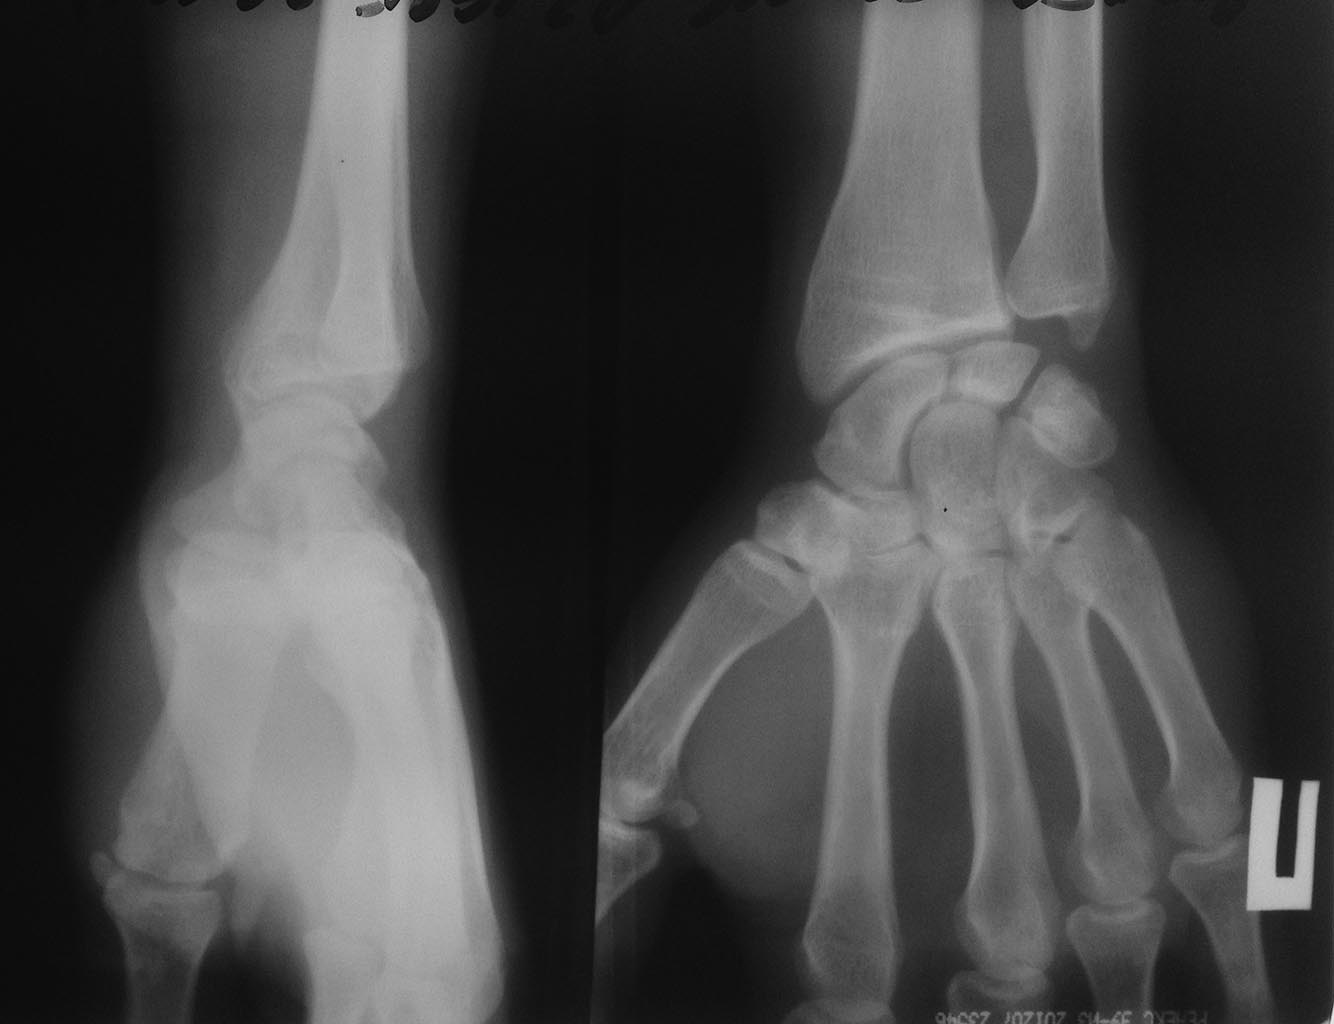

мужчина 32 лет беспокоят боли в правом лучезапястном суставе.

6 месяцев назад появились боли при движении в правом лучезапястном суставе при физических нагрузках ( отжимания) постепенно боли усилились. Боль локализована в проекции шиловидного отростка локтевой кости, в покое боли нет.

На данный момент движения резко ограничены. проходил два курса лечения ( НПВС , МАГНИТ, мази, сероводородные ванны) - никакого эффекта, только ухудшение. Я третий травматолог к которому он обратился.

На свежем снимке похоже импрессия трехгранной кости?? направлен на МРТ. что может быть? как лечить? блокаду гормоном не предлагать)

Необходимо исключить подвывих головки локтевой кости (Эссекс-Лопрести?) Необходимо рентгенография обоих лучезапястных суставов в чётких прямой и боковой проекциях, при возможности, МСКТ. Не исключается артроз в зоне полулунно-головчатого сочленения (субхондральный склероз полулунной кости)